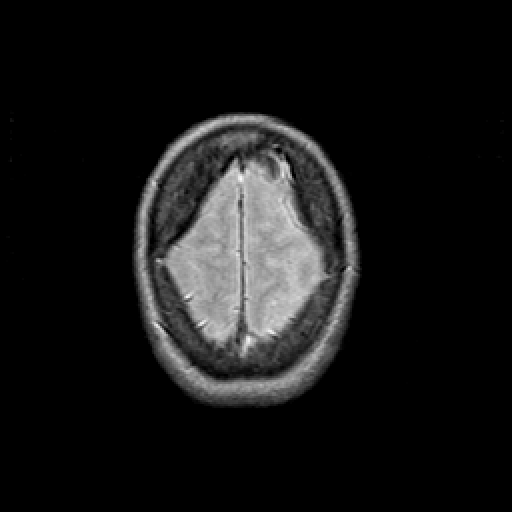

Proton density-weighted structural MR: Slice 47

Slice 47